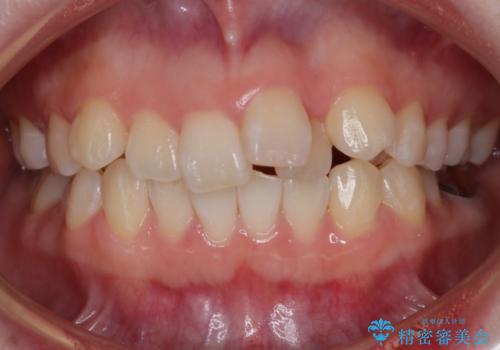

【モニター】八重歯と正中を改善 ワイヤー装置の抜歯矯正

担当医 藤巻太一朗